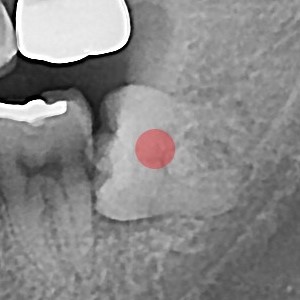

智齿拔除 完全埋伏智齿

b047bd763797d0ee5fe0c71c12970e9f_1766119523_1974.jpg